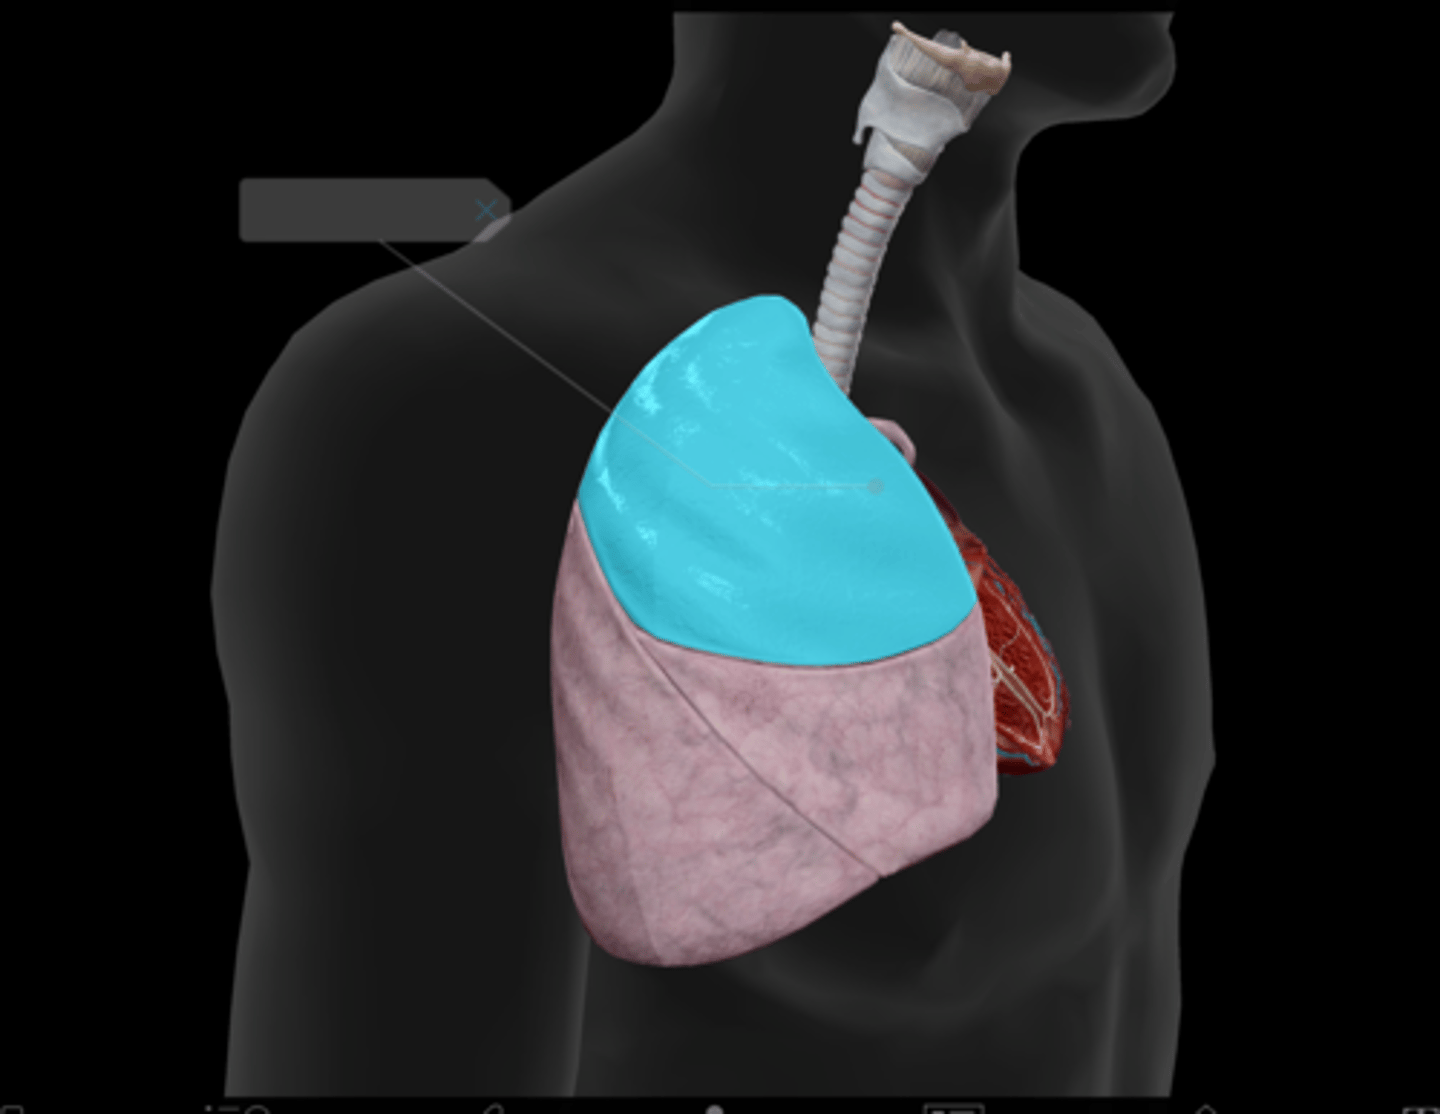

Superior lobe

Middle lobe

Inferior lobe

Horizontal fissure

Oblique fissure